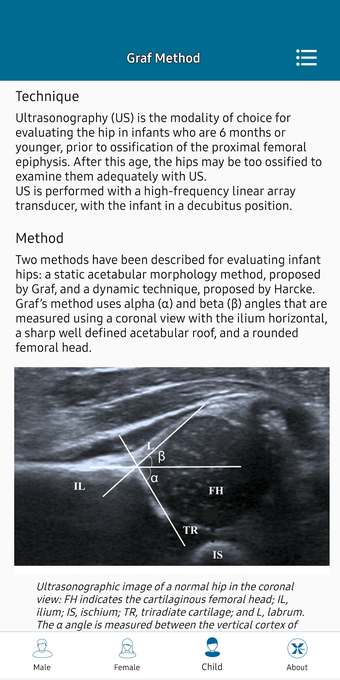

This helpful app is intended for all those who practice medical imaging and for the radiologists who use the application in their work. It is an atlas of the main measurements in radiology and their normal values, divided into six subspecialties: osteoarticular, cervical region, thorax, cardiovascular, abdomen, and pelvis.